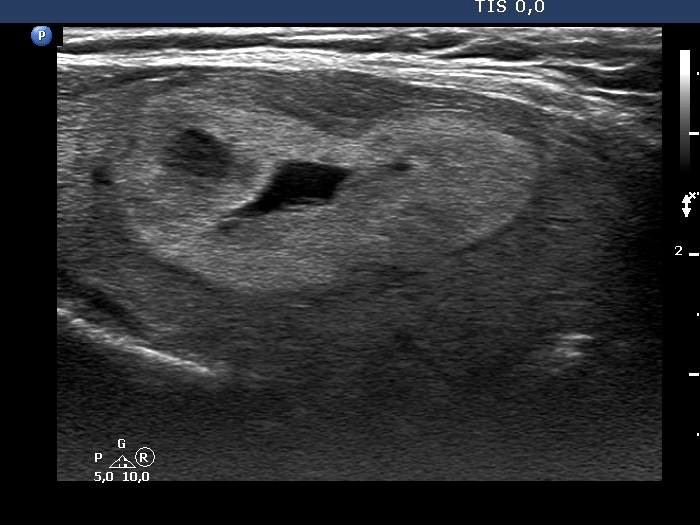

The composition of the nodule - case 1530 (ultrasonographic picture 10)

Right lobe, longitudinal scan